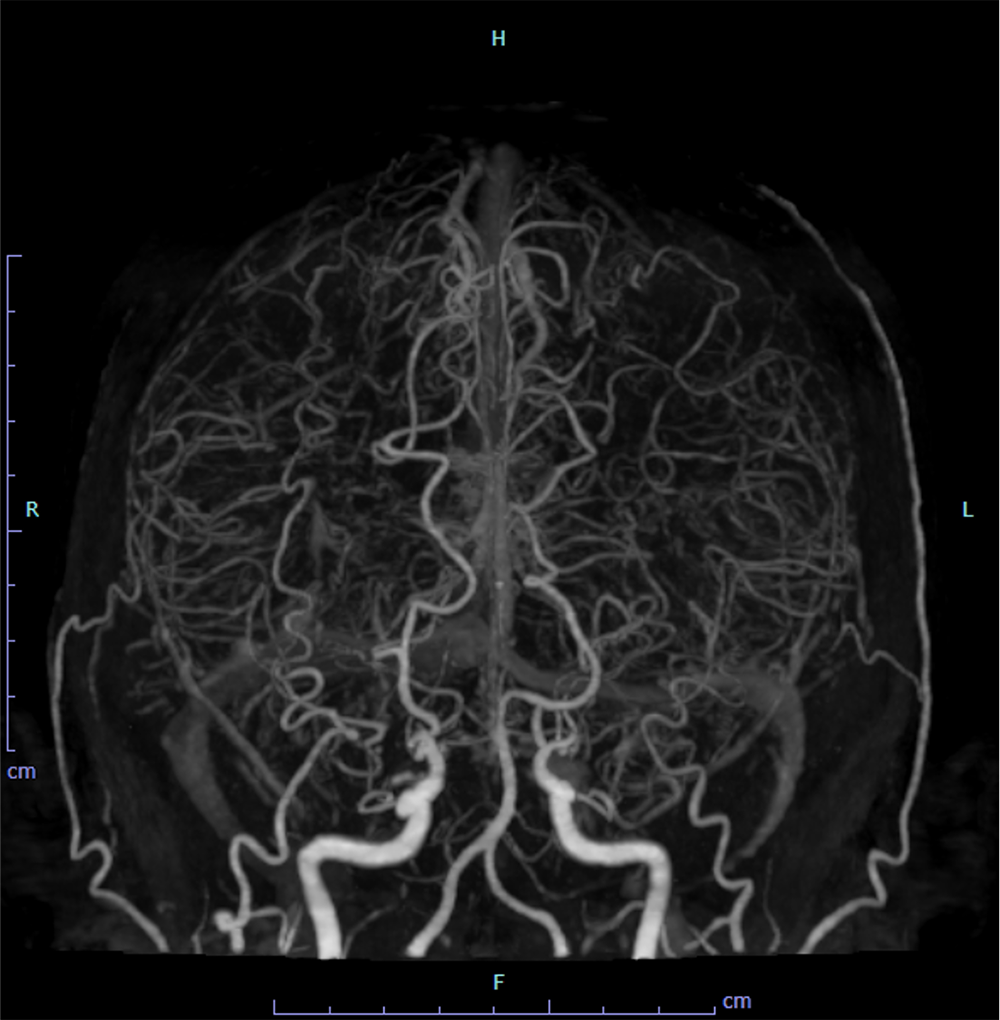

14歳ごろから手足の痺れやめまいなどを自覚しており、兄弟のもやもや病による脳卒中を契機にMRI撮像され、もやもや病と診断された。CTAで両側内頸動脈は閉塞しており、周囲に微細な増生血管をみとめた。前大脳動脈や中大脳動脈は狭窄しており、両側後大脳動脈に拡張を認めた。脳血流SPECTで左前頭葉、側頭葉に血流低下を認め、間接的血行再建術が施行された。

もやもや病における新生血管(もやもや血管)は血管径が細く、通常の撮影では明瞭な描出が難しいことがある。100kVの低管電圧撮影を用いることでもやもや血管の微細なネットワークを鮮明に描出し、病状評価や治療計画立案に役立てている。

血行再建術では、STA-MCAを直接吻合する方法のほか、STA、DTA、MMAなどを脳表と接続する間接血行再建術も広く施行されており、末梢の微細な血管解剖の取得までもが必要となる。

CT技術や撮像プロトコル設定について